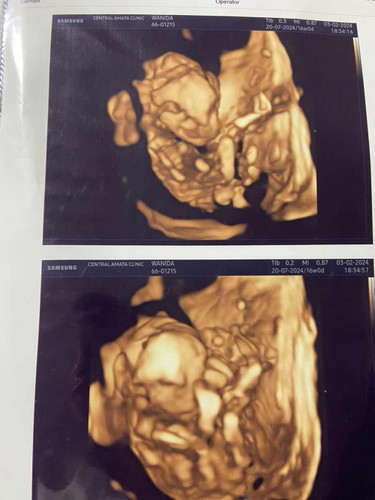

แม่ช่วยดูหน่อยค่ะ น้องปากแหว่งไหมคะ เเม่ไม่เเน่ใจเลยค่ะ รุปที่2ดูปกติ ท้องเเรกค่ะ หมอบอกต้องซาวดูเรื่อยๆ เลยมาถามเเม่ๆดูค่ะ 16wค่ะ

ต้องรอประมาณ 5-6 เดือนค่ะ จะเห็นชัดกว่านี้